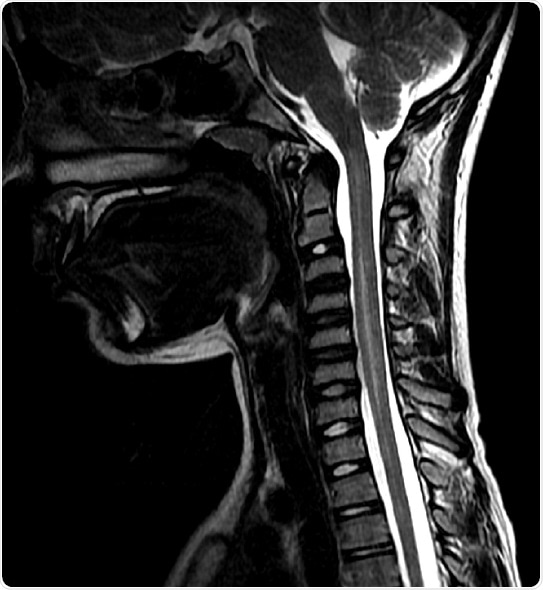

The Centers for Disease Prevention and Control (CDC) defines AFM as weakness in one or more arms or legs as well as damage to the gray matter of the spinal cord as detected by magnetic resonance imaging (MRI). But, the researchers thought that other illnesses that affect the spinal cord and nervous system were getting lumped in with the AFM cases

Those patients with definitive AFM had a fever or viral infection before the onset of weakness in the arms or legs. They also lost function of their limbs in one side of the body first with the majority of children losing function of a single limb or all four eventually. The children with definitive AFM also had many white blood cells in their spinal cords, and less protein in their cerebral spinal fluid than the children with alternative diagnoses. And the children with AFM had only had damage in the spinal cord’s gray matter ¾ where the bodies of the nerve cells reside ¾ and not in the white matter—where the connections between nerve cells that send messages back and forth reside—or the brain like those cases with alternative diagnoses. Children with AFM respond better with infusions of immunoglobins—a collect of antibodies that can help tag pathogens as invaders so the immune system can eliminate them.

The most common alternative diagnoses were transverse myelitis—an inflammation of the spinal cord—and spinal cord stroke. Other diagnoses included demyelinating syndromes, Guillain-Barre syndrome, Chiari I myelopathy and meningitis. Using immune suppressants are ideal for reducing inflammation in the spinal cord in diseases such as transverse myelitis, but this could be detrimental to patients with AFM.